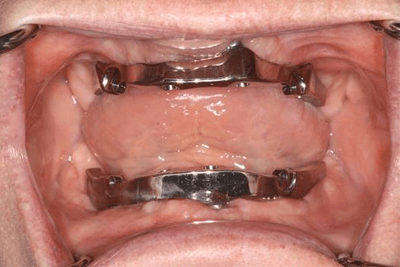

Teeth were removed and implants were placed and a bar was fitted to splint the implants for the upper jaw.

Delivery Day! Note the shape of the denture – no coverage on the roof of the mouth. This allows for less speech impairment and allows you to taste foods the same.

This is what the inside surface of a removable implant retained denture looks like – the side that connects to the bar.